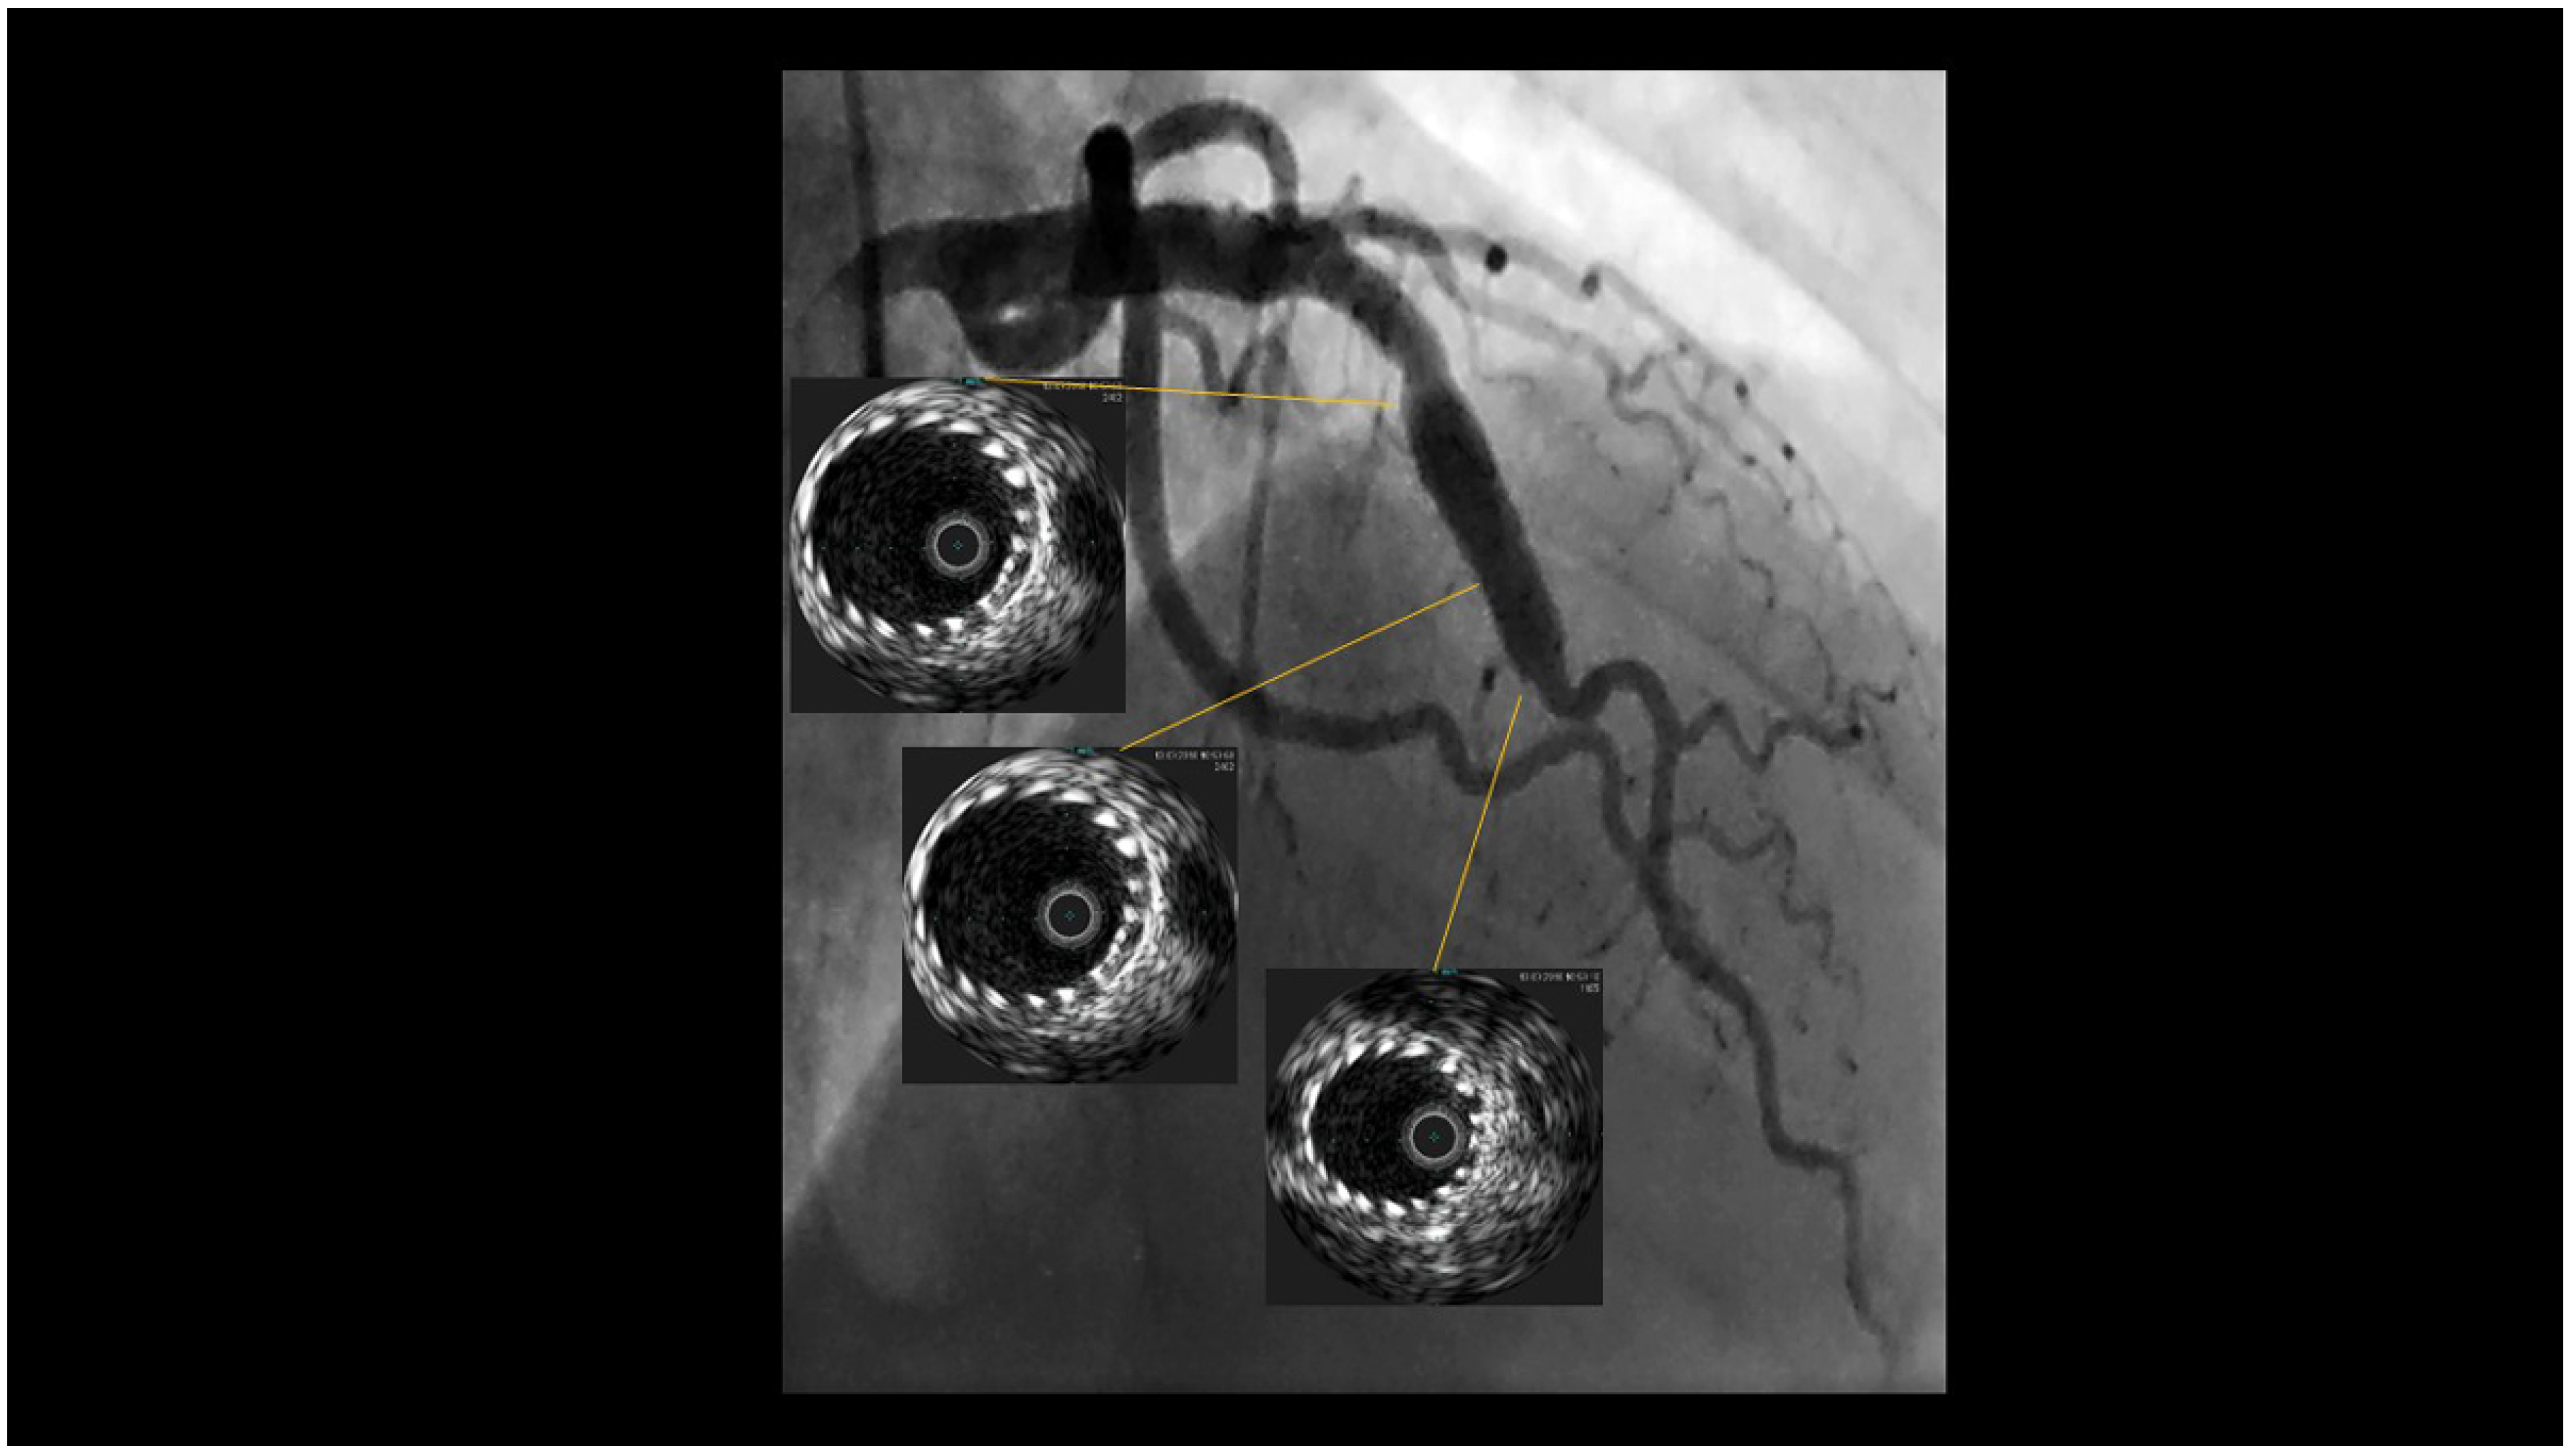

Fusiform Mid-LAD Aneurysm Due to Passive Arterial Wall Dilatation After Implantation of a Self-Expandable Stent